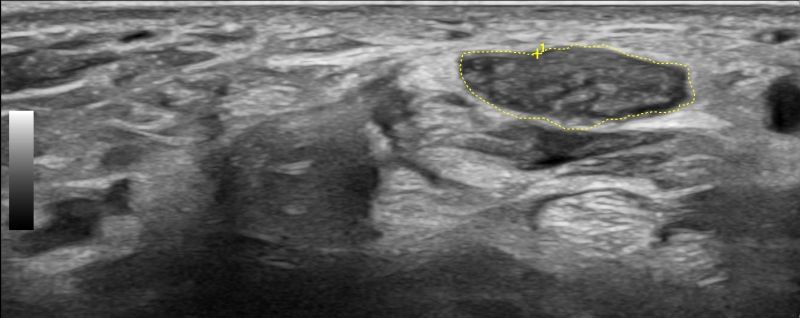

Hand Ultrasound examines joints, tendons, ligaments, nerves, and soft tissues of the hand. Pathologies that can be diagnosed by Hand Ultrasound are numerous, including:

Soft Tissue Pathologies

- Ganglia

- Tumors